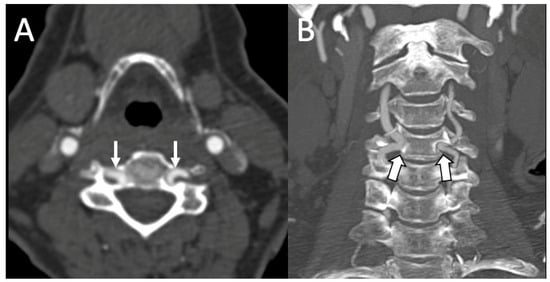

3.1. Variations in the V2 Segment